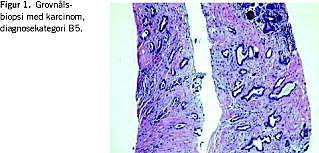

Fordelene ved grovnålsbiopsi (Figur 1 ) er mange og veldokumenterede [2, 5]. Metoden har været anvendt i Danmark i mange år og anvendes i dag af såvel kirurger som specialister på de billeddiagnostiske afdelinger. Tilstedeværelsen af mikroforkalkninger kan bekræftes med denne metode, og læsionen kan karakteriseres bedre end ved FNAC. Det er her muligt at skelne mellem invasivt karcinom og karcinom in situ. Der er imidlertid den ulempe, at selv om det blot er en minimal vævscylinder, som udhentes, så er der grænser for det antal biopsier, man kan udtage fra samme læsion. Det betyder, at undersøgelsen af heterogene forandringer kan være ufuldstændig.